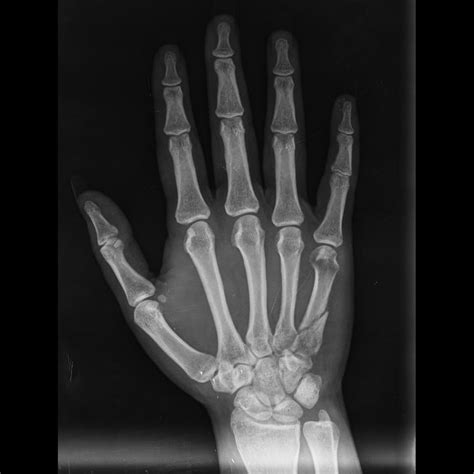

A broken hand x-ray is a type of medical imaging that uses low levels of radiation to produce images of the bones in the hand. These images are crucial for diagnosing fractures, dislocations, and other bone-related injuries. The x-ray machine emits X-rays that pass through the body and are absorbed differently by various tissues. Bones, being denser, absorb more X-rays and appear white on the resulting image, while softer tissues appear darker.

• Fracture Lines: These appear as thin, white lines on the x-ray image and indicate a break in the bone.

• Displacement: This refers to the misalignment of the bone fragments, which can affect the healing process and may require surgical intervention.

• Angulation: This is the angle at which the bone fragments are displaced, which can also impact the treatment plan.

• Soft Tissue Injuries: While x-rays primarily show bones, they can also reveal swelling or other soft tissue injuries that may be associated with the fracture.